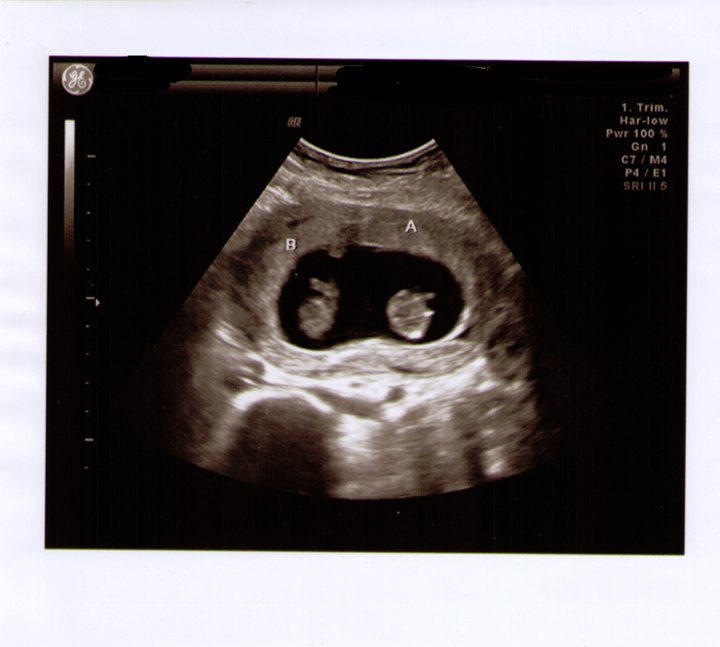

![]() | |

| This is an ultrasound picture of our twins; it just amazes me every time I see it! |